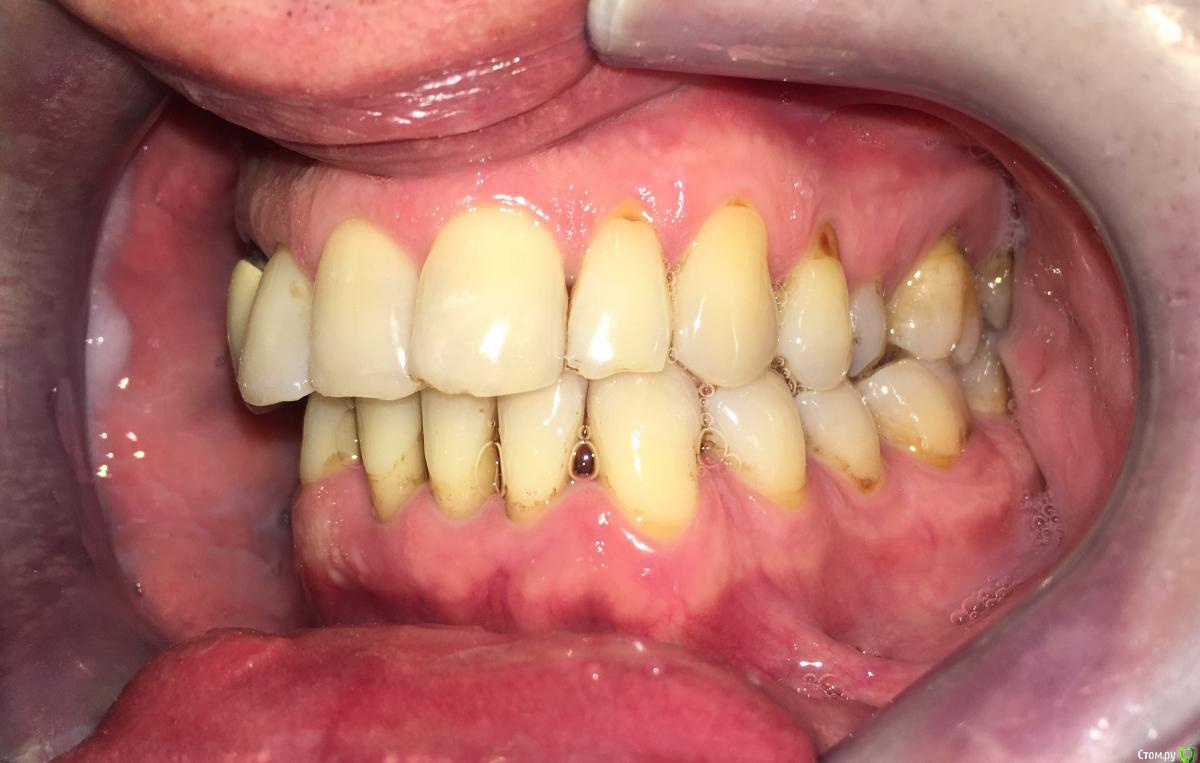

Nitrino1 Опубликовано 20 января, 2018 Поделиться Опубликовано 20 января, 2018 Коллеги помогите поставить правильный диагноз и составить план лечения, чтоб продолжительно держалосьОбъективно на всех зубах камни над и поддесневые. В 47ом зубе 3-я степень подвижность.Почистил все камни и налеты, назначил полоскание, пасту Парадонтах, удалил 47ой зуб.Сделал панорамку (до удаления) и фотки тоже до удаления.Должен составить план лечения... Ссылка на комментарий

red_butler Опубликовано 21 января, 2018 Поделиться Опубликовано 21 января, 2018 Хронический генерализованный пародонтит тяжелой степени, в ремиссии (по МКБ-10 Хронический генерализованный пародонтит, код К0531) Ссылка на комментарий

Nitrino1 Опубликовано 21 января, 2018 Автор Поделиться Опубликовано 21 января, 2018 Хронический генерализованный пародонтит тяжелой степени, в ремиссии (по МКБ-10 Хронический генерализованный пародонтит, код К0531)какой план лечения вы бы порекомендовали? интересует момент с нижними резцами, их шинировать или же удалить? на верхних 6ках тоже ситуация не очень. Вообще какую тактику выбрали бы?И еще просьба, посоветуйте что можно почитать современное на тему парадонтитов и парадонтозов, то что у меня есть это старое уже Ссылка на комментарий